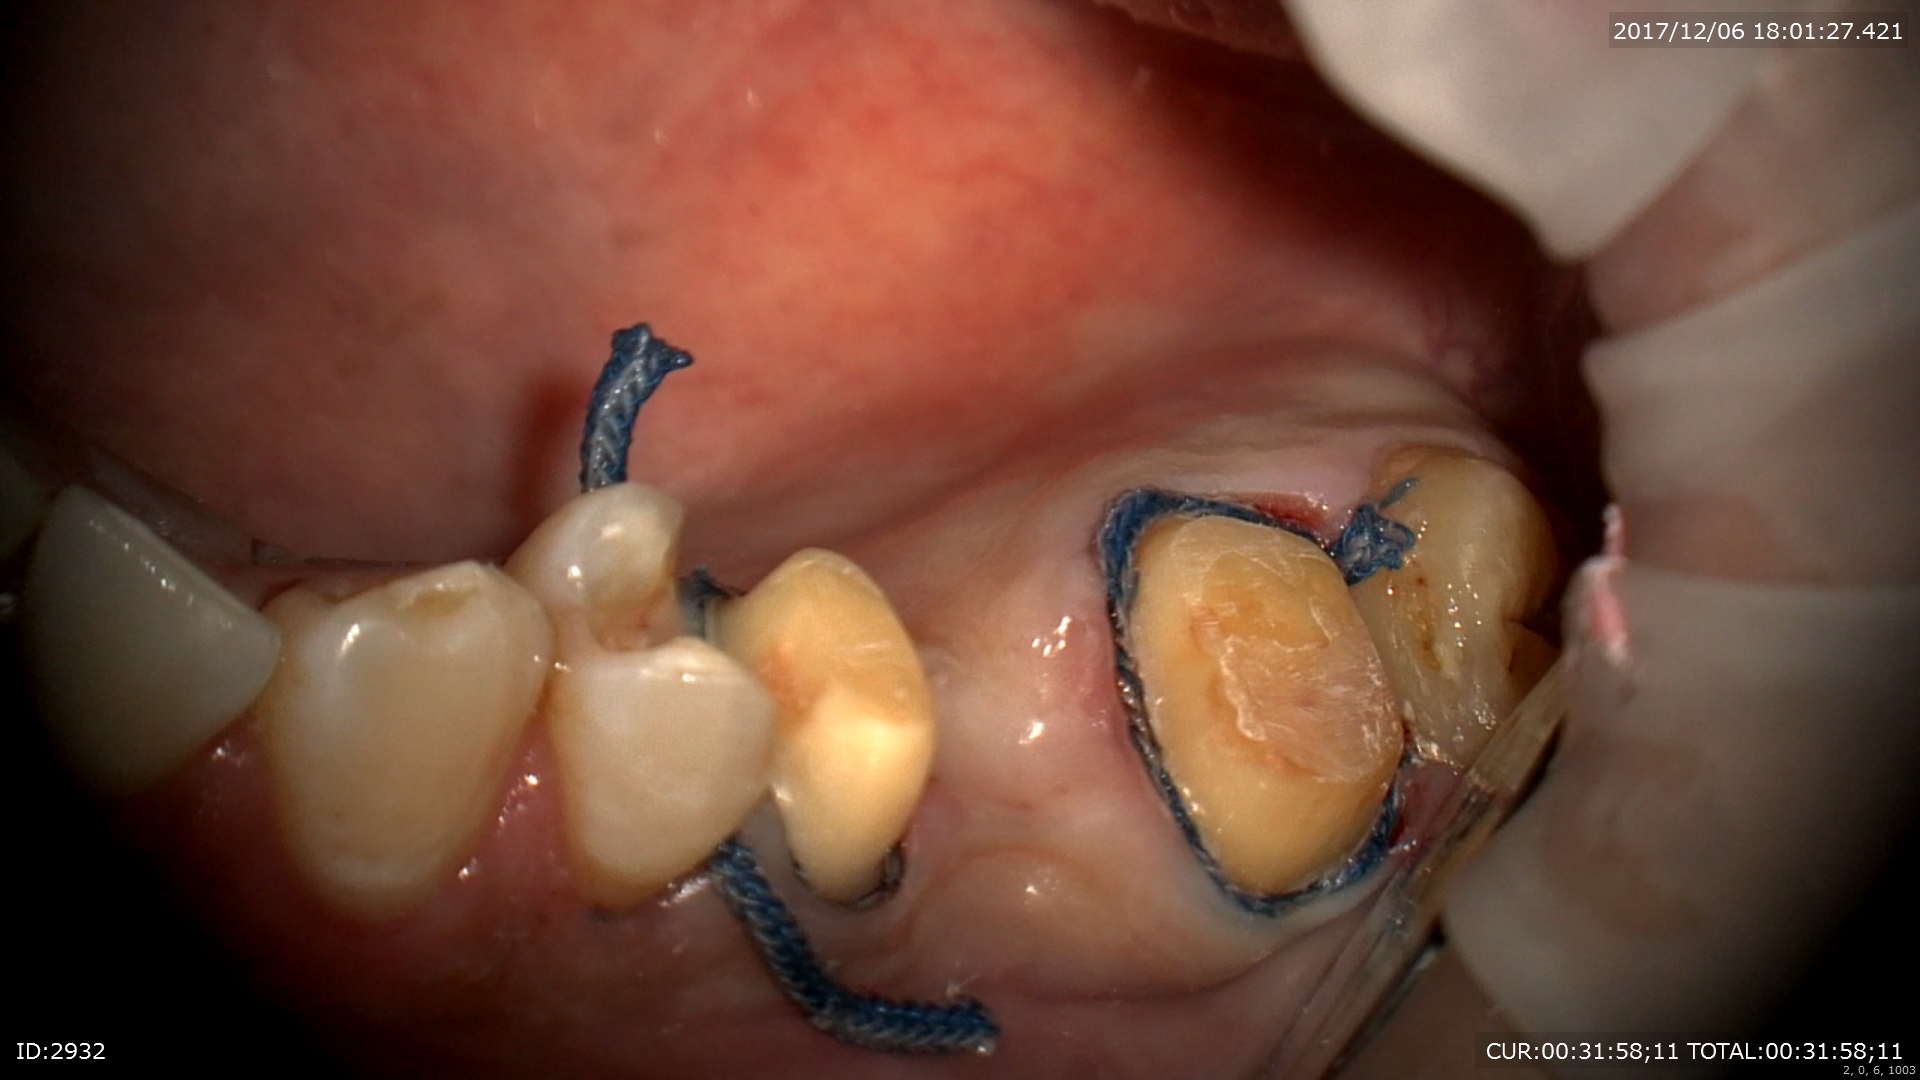

2ケース目:ブリッジの型とり

精密な型取りの為の為、形を整えて。

糸で圧排(無痛下)

次回は本物以上の歯が入りますよー。